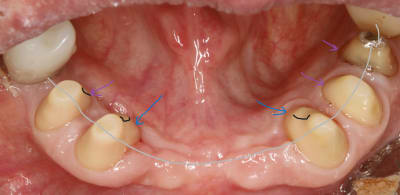

bon , revenons à notre affaire , quel rapport entre la conicité et l occlusion ? .

le rapport le voilà , je remets ici la photo du prov au bout de 3 mois , avec les traits orange .

de toute évidence il y a des faces d usure à gauche qu il n y a pas à droite .

donc même sans parler pb occlusal , si je veux faire la prothèse , il faudra au minimum que je sois homothétique à ces pistes .

ce qui va m obliger à rentrer les moignons en lingual . pcq de toute évidence , lui il n a qu une envie c est d aller à gauche . et s il y est allé avec les prov , il y retournera avec les vrais

maintenant regardes bien la photo vue de haut que je remets .tu le vois le trait gris ?

c est l alignement de la ligne de crête . et cà c est fondamental pcq c est ce qui préfigure la courbe de Wilson et Monson .

c est ce qui fait qu il y aura une stabilité ou pas .

bref , le fait d aligner les sommets va t obliger à incliner les moignons si besoin .

elle vient de là la conicité du bordel global . :-)

et non pas d ailleurs , ce n est pas un choix de style de taille , c est une obligation architecturale .

bien , on a aligné la tête des moignons sur la courbe , mais pour des raisons évidentes de stabilité de la prothèse , on va aussi les aligner dans le plan horizontal , c est quand même mieux pour éviter les bascules , non ?

alors oui tu risques d avoir des trognons coniques .

et c est là que tu ressors le congé . c est en faisant les congés en vest que tu rentres le pied des dent et donc que tu réduis la conicité .

conicité , je le rappelle , par exemple , entre vest de 44 et de 34 , hein , faut pas l oublier ça . sinon c est la contre dépouille direct .

mais tu comprends aussi tres vite que plus ton congé est large plus tu perds de la rétention , puisque si tu prends une grosse fraise , en quart de rond , toute la partie arrondie va te faire une découpe horizontale qui elle ne te servira à rien quand à la rétention par contre elle te servira à bien niquer la dent .

moralité le gros congé ça ne peut pas aller .

a la limite tu peux faire un double congé en espérant rajouter un peu de partie verticale .

ici sur les canines ça nous arrange pour avoir des dents plus fines .

traits noirs sur la photo .